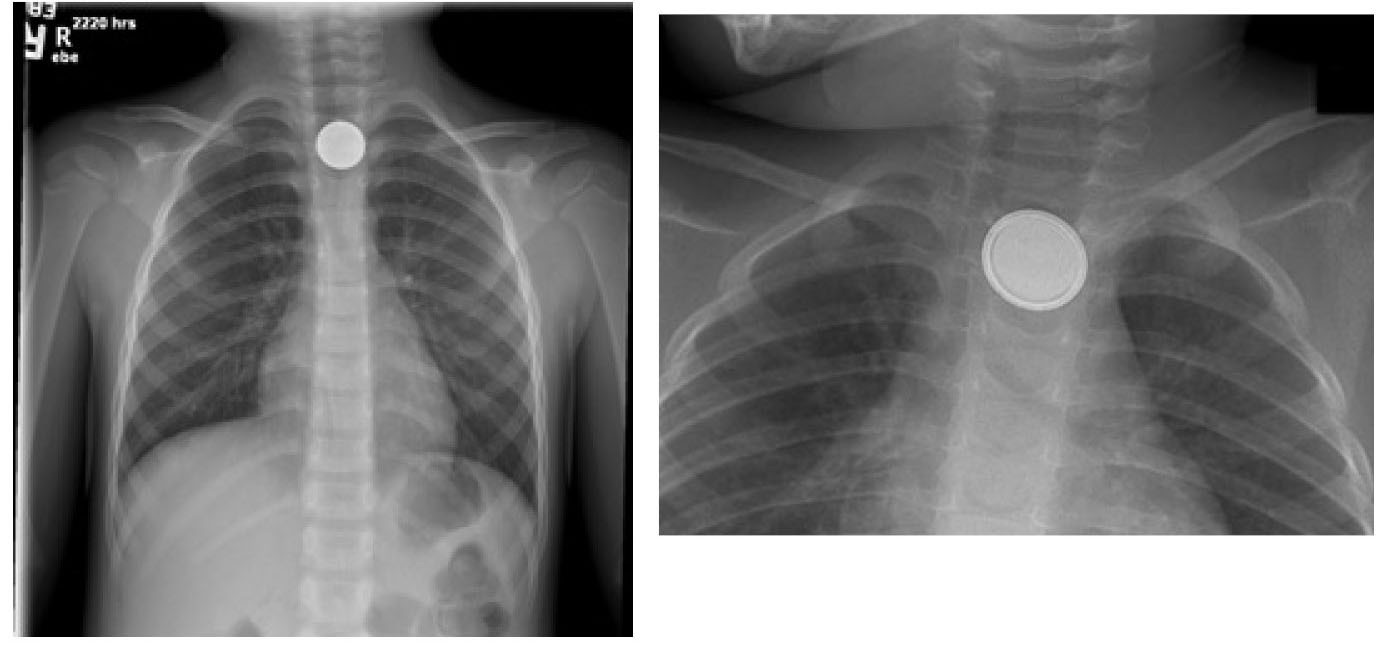

Anteroposterior and lateral plain films of the chest should be obtained.2,21 Also obtain abdominal radiographs in a patient without symptoms but with a history of button battery ingestion.2,21 The presence of a double ring or halo sign on an anteroposterior projection and a step-off sign on a lateral projection will help to differentiate a button battery from a coin.2,20-22 (See Figure 1.) Small, thin batteries may not have a reliably visualized step-off or halo sign because of their size.20

Figure 1. Coin and Button Battery Appearance on Anteroposterior Chest X-Ray |

![]() |

Left: Coin in upper esophagus; Right: Button battery on X-ray; note “double halo” Images courtesy of: Chad D. McCalla, MD, and Crick Watkins, DO. |